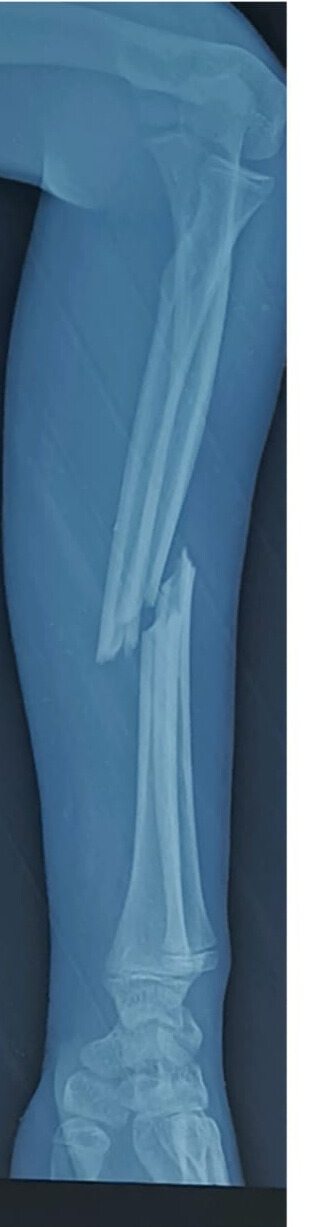

Preoperative Findings:

The X-ray shows a displaced diaphyseal both-bone forearm fracture with an oblique fracture pattern of the radius and ulna.

At Medical Center, Pune, a complex forearm injury involving a Diaphyseal Segment Radius Simple Oblique Fracture and a Diaphyseal Segment Ulna Simple Oblique Fracture was successfully managed using advanced internal fixation techniques.

A 32-year-old patient, weighing 73 kg, presented with a significant injury to the mid-shaft region of both forearm bones. To restore alignment, stability, and functional rotation, the surgical team proceeded with internal fixation.